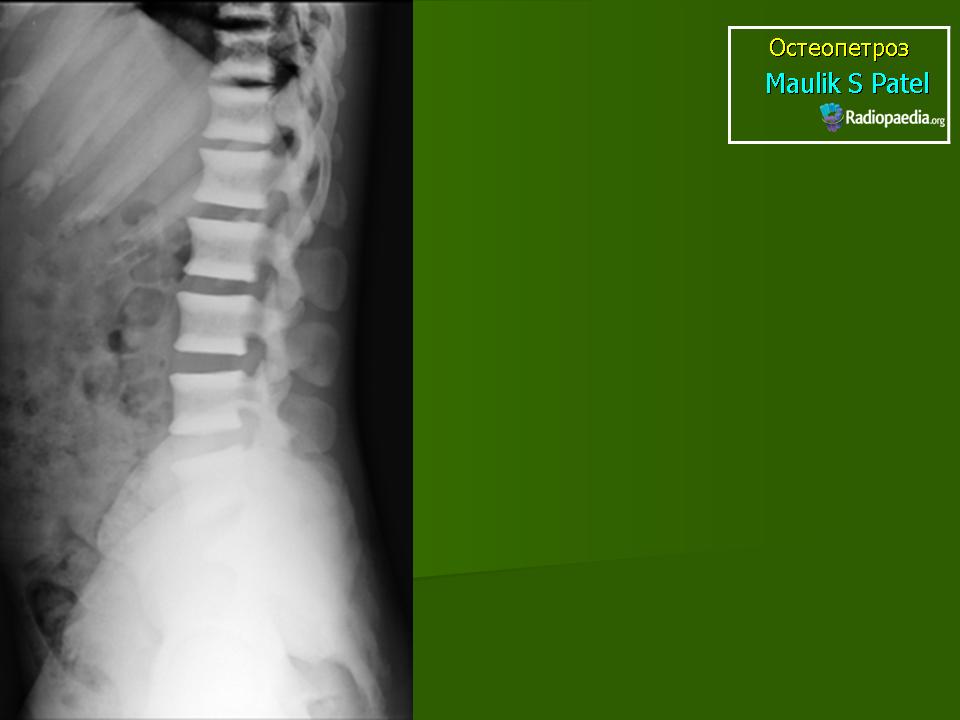

Лабораторная и инструментальная диагностика. Характерны гипокальциемия, гипофосфатемия и повышение уровня ПТГ в сыворотке (вторичный гиперпаратиреоз). Всасывание кальция в кишечнике усилено, но гипокальциемия тем не менее сохраняется, поскольку ПТГ не активирует остеокласты. При рентгенографии и денситометрии костей обнаруживают их равномерное уплотнение и увеличение костной массы; компактное и губчатое вещество имеют одинаковую плотность. При гистологическом исследовании биоптатов кости выявляются толстые прослойки неминерализованного органического матрикса, иногда встречаются признаки остеомаляции (рахита). Количество остеокластов нормальное или даже увеличенное, но они малоактивны.

Мраморная болезнь (болезнь Альберс-Шенберга) - семейный генерализованный остеосклероз, протекающий с лейкемической реакцией крови у детей, с анемией и лейкопенией у взрослых, нередко с атрофией зрительных нервов и глухотой. Характерны деформация мозгового и лицевого черепа, заращение придаточных полостей носа плотной бесструктурной костной тканью. Ввиду постепенного сужения отверстий в черепе и межпозвонковых отверстий могут возникать полиморфные проявления поражения периферической нервной системы как на черепном, так и на позвоночном уровнях. В позвонках костные балки губчатого вещества утолщены и уплотнены. В трубчатых костях отмечается сужение, а затем и исчезновение костномозговых полостей, эпифизы булавовидно утолщены и поперечно исчерчены, имеется склонность к патологическим переломам. Наследуется по аутосомно-рецессивному типу и тогда, проявляясь в фенотипе в первые годы жизни, быстро приводит к смерти, или же - по аутосомно-доминантному типу, проявляясь в 20-40-летнем возрасте. Описал болезнь в 1907 г. Н.Е. Albers-Schonberg.